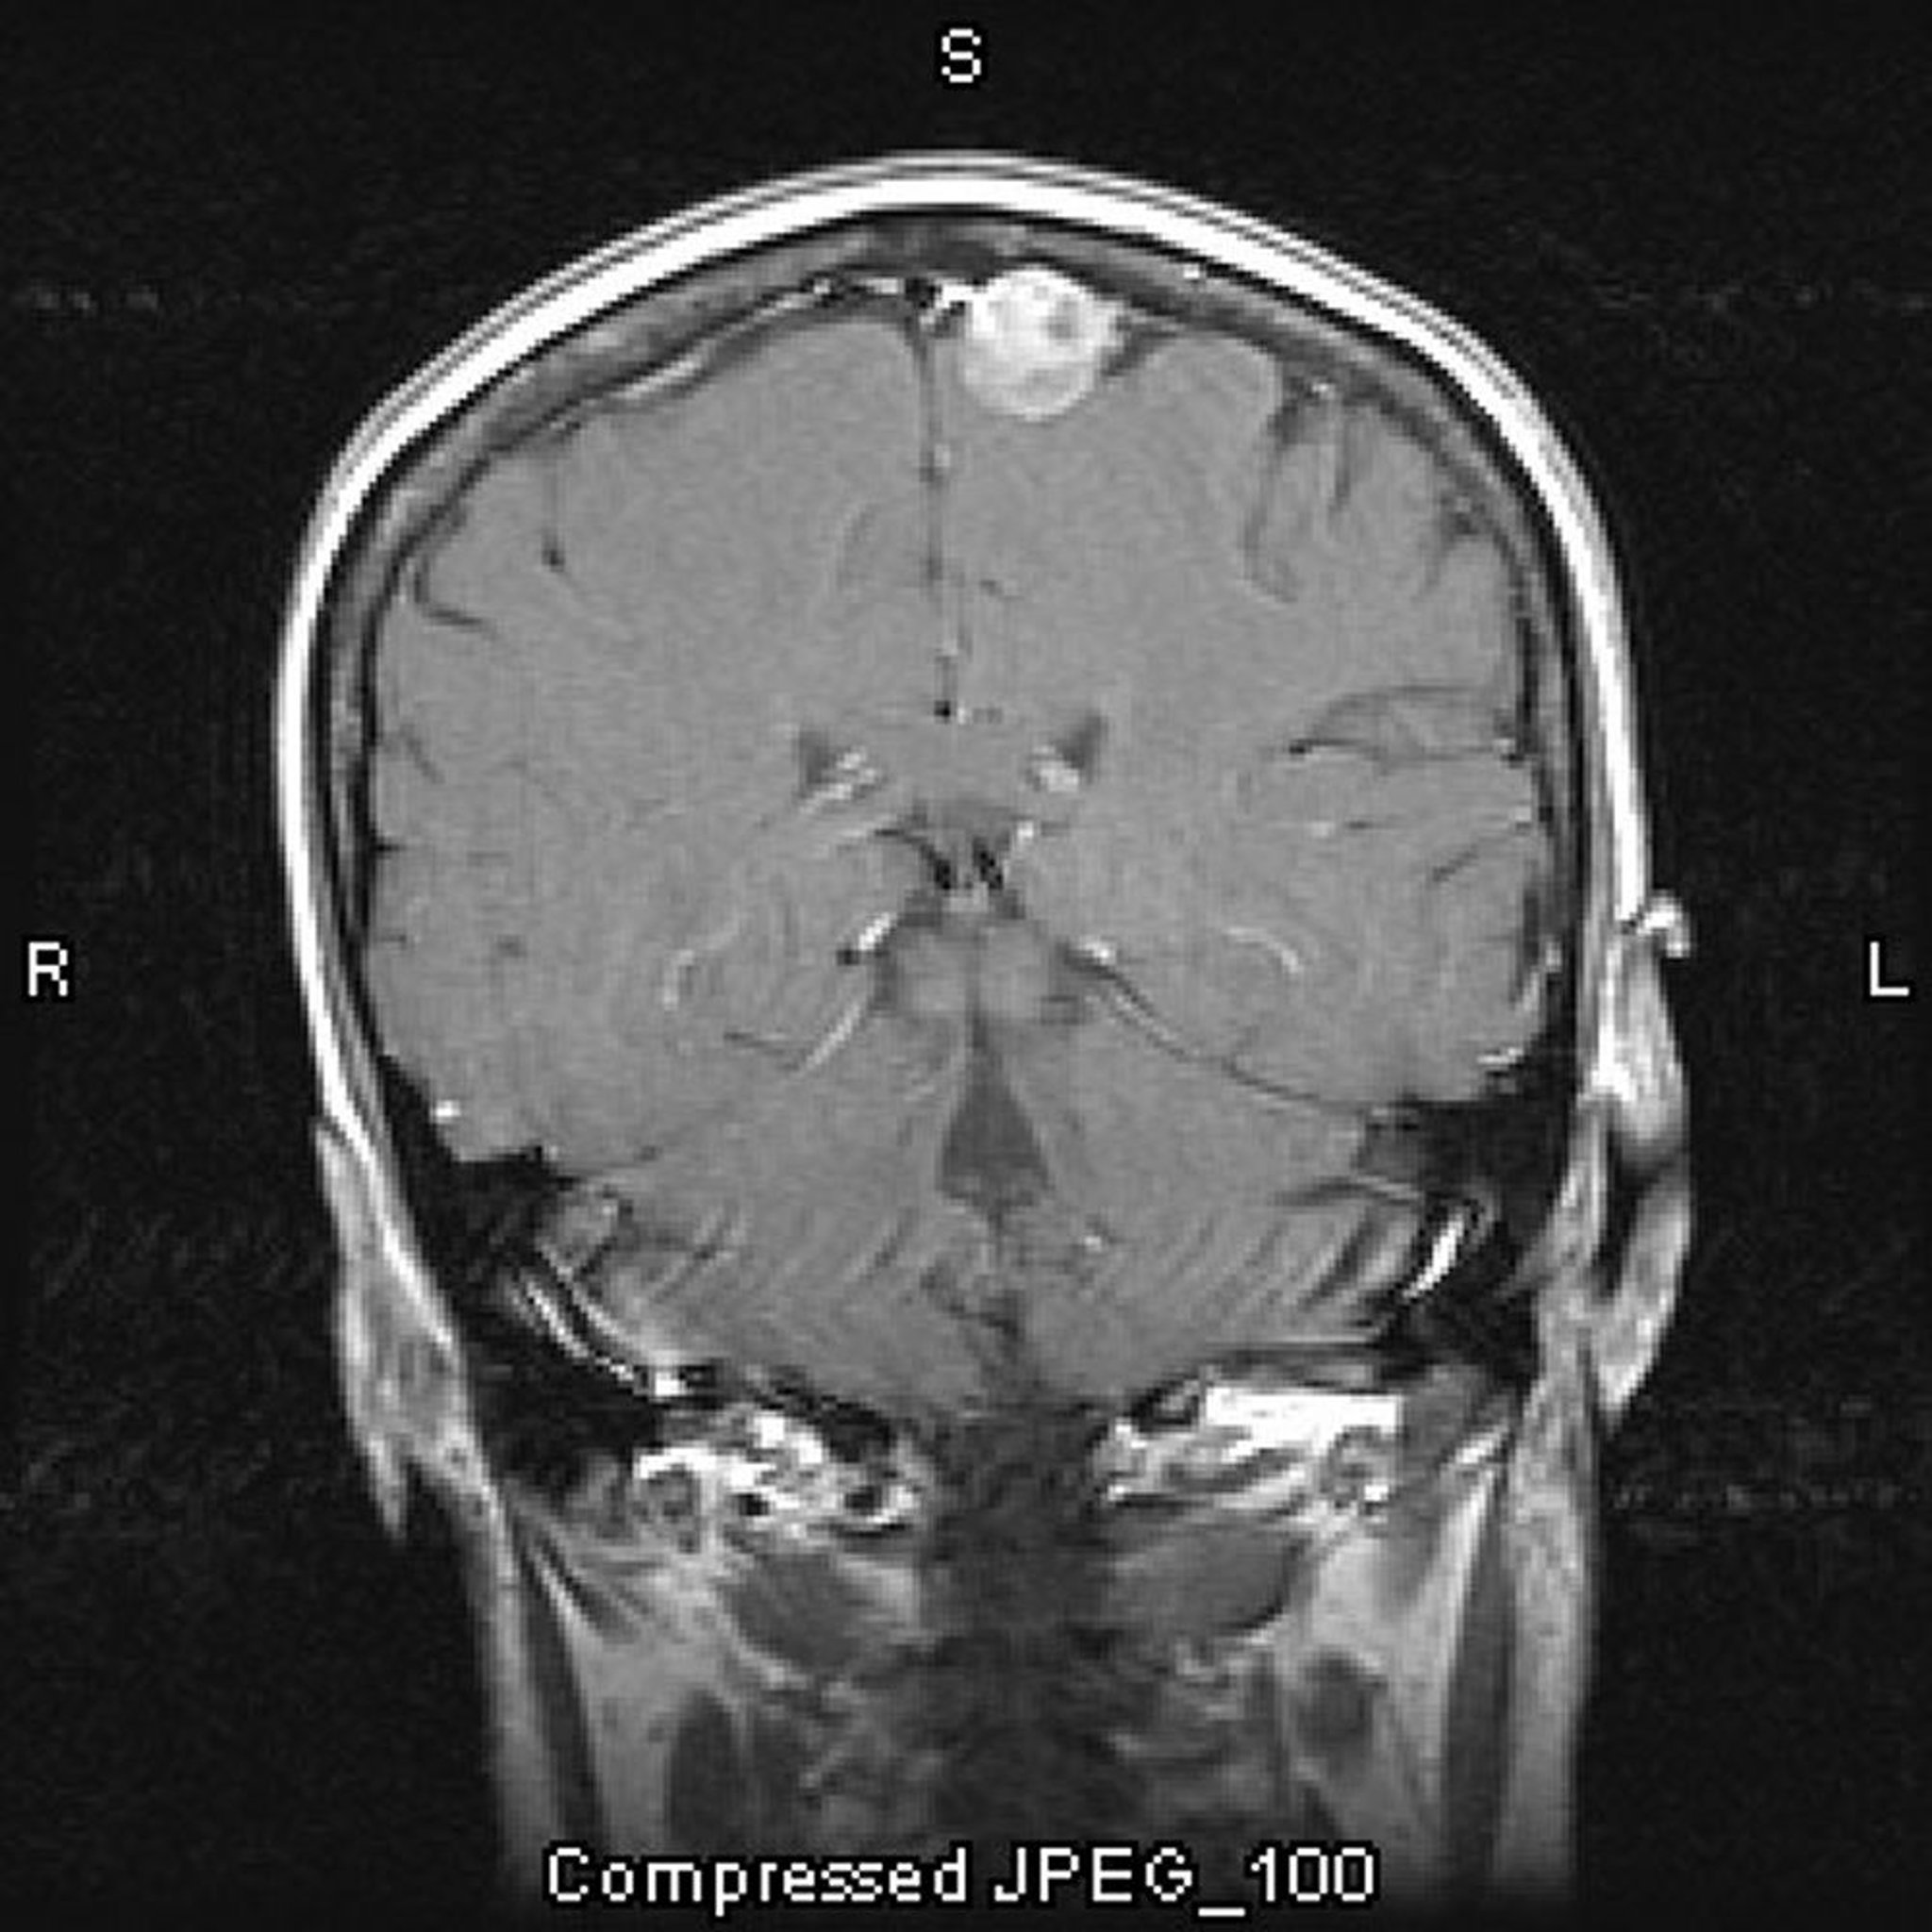

Meningioma, parassagital

Essa RM com contraste mostra um meningioma. A localização parassagital é típica dos meningiomas.

Imagem cedida por cortesia de William R. Shapiro, MD.